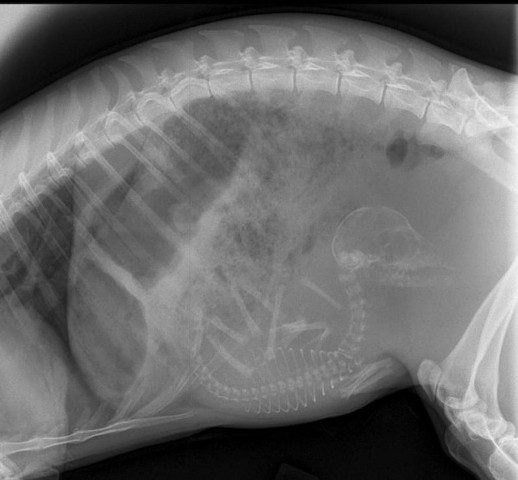

Մենք բոլորս լավ պատկերացնում ենք, թե ինչպես է անցնում մարդու հղիությունը, և շնորհիվ ժամանակակից տեխնոլոգիաների՝ կարող ենք տեսնել երեխային մայրիկի արգանդում հղիության ամենավաղ փուլում։ Իսկ ինչպե՞ս է ընթանում կենդանիների հղիությունը։ Մասնագետները, ովքեր հոգ են տանում հղի կենդանիների մասին, ներկայացրել են նրանց ռենտգենային և ուլտրաձայնային լուսանկարները, որոնք ձեր դատին է հանձնում «twizz.ru» կայքը։

Կրիա